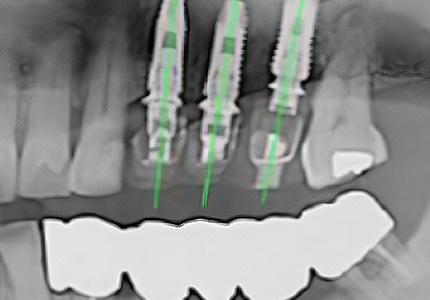

• 가이드 장착 후 수술

제작된 가이드를 수술 전 구강에 장착 후 계획한 위치에 체계적인 수술로 오차 범위를 줄입니다.

모의수술로 계획한 위치에

내 치아 같은 보철물로 자연스럽게 임플란트

식립

이 가능합니다.